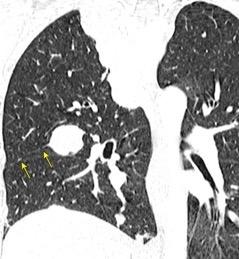

Hallazgos en TC de invasión local Fiabilidad diagnóstica: 62,7-72,3%.

Valor predictivo positivo: 41,1%-56,4%.

La predicción basada en TC es un falso positivo en casi 50% de los casos

Adenocarcinoma poco diferenciado predominio acinar.

Kim H et al. CT-defined Visceral Pleural Invasion in T1 Lung Adenocarcinoma: Lack of Relationship to Disease-Free Survival. Radiology 2019

Du X et al. The Value of 18F-FDG PET/CT in the Diagnosis of Tuberculous Pleurisy and in the Differential Diagnosis between Tuberculous Pleurisy and Pleural Metastasis from Lung Adenocarcinoma. Contrast Media & Molecular Imaging. 2022

Adenocarcinoma pulmonar